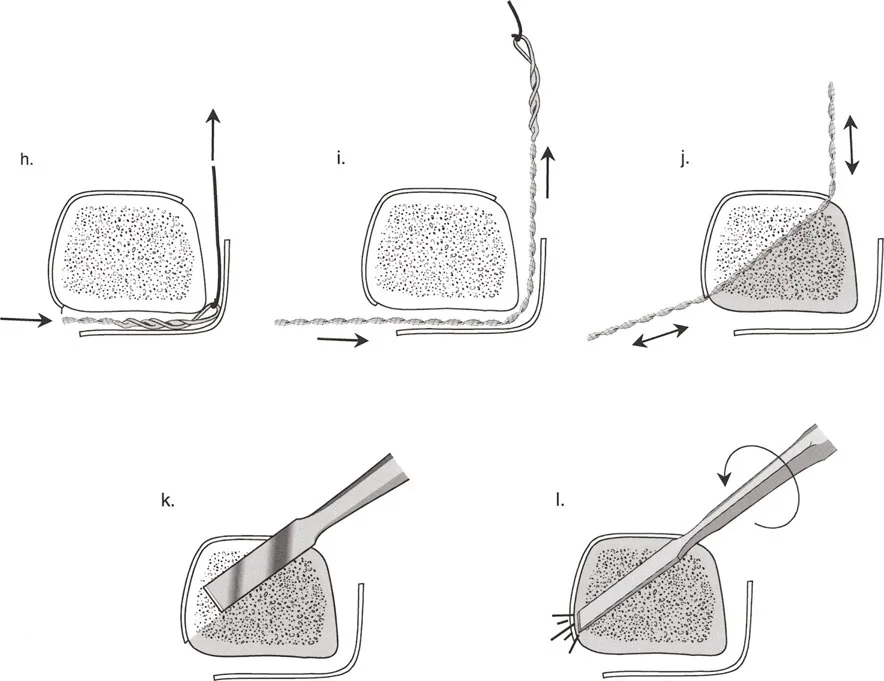

قيود الأسلاك والدبابيس في القاعدة 2

لتحقيق هذه الترجمة الضرورية والمقصودة بسلاسة باستخدام إطار دائري كامل الأسلاك، يلزم استخدام أسلاك الزيتون المعاكسة (counter-opposed olive wires). تعمل أسلاك الزيتون كقوى سحب ديناميكية، تسحب قطعة العظم على طول الحلقة أثناء فتح المفصلات. بدون أسلاك الزيتون، سيبقى العظم ثابتًا بينما تتحرك الحلقة عبر الأنسجة الرخوة، مما يسبب نخرًا شديدًا في الجلد.

على العكس من ذلك، إذا تم استخدام دبابيس نصفية (مسامير شانز)، فإنها تقيد العظم بطبيعتها بالحلقة. نظرًا لأن الدبابيس النصفية هي أذرع صلبة (مثبتة من طرف واحد بالحلقة ومغروسة في العظم من الطرف الآخر)، فإنها لا تسمح للعظم بالانزلاق على طول محور السلك. هذا يجعل أسلاك الزيتون غير ضرورية للترجمة في منشآت الدبابيس النصفية، ولكنه يتطلب من الجراح التأكد من أن الدبابيس النصفية قوية بما يكفي (عادةً دبابيس بقطر 5 مم أو 6 مم مطلية بهيدروكسي أباتيت) لتحمل لحظات الانحناء الناتجة عن الترجمة.

| تقابل الأسلاك | استخدم ما لا يقل عن سلكين زيتون متقابلين لكل قطعة إذا كنت تتجنب الدبابيس النصفية. | الأسلاك الزيتون الفردية ستسبب قصًا ودورانًا غير مرغوب فيه حول محور السلك. |